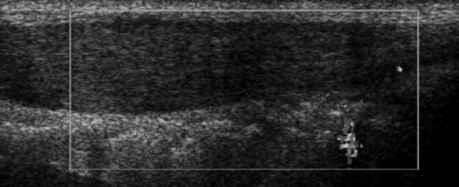

Normal US appearance of Achilles tendon

Common Achilles tendon pathology

Tendinopathy

Partial or complete tears

Retrocalcaneal bursitis